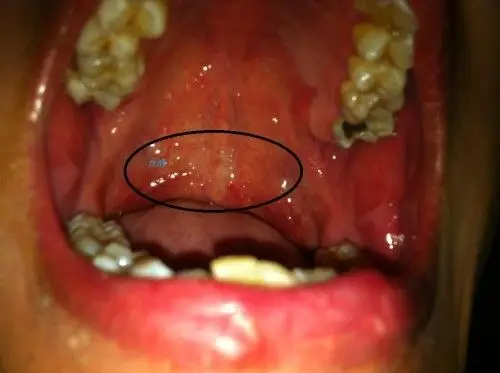

软腭上有小疙瘩图片

软腭上面有许多小水泡. 咽喉疼痛,去第二医院说没什么问题.

我想问下软鄂上有个小白疙瘩是硬的难道口腔溃疡长这里是凸起来的吗?

大家帮我看看,嘴巴上颚长了小点点,用舌头舔能感觉到,不疼不痒 怎么了

我两侧软腭一个一个黑色点是什么东西啊,还有上颚的小颗粒